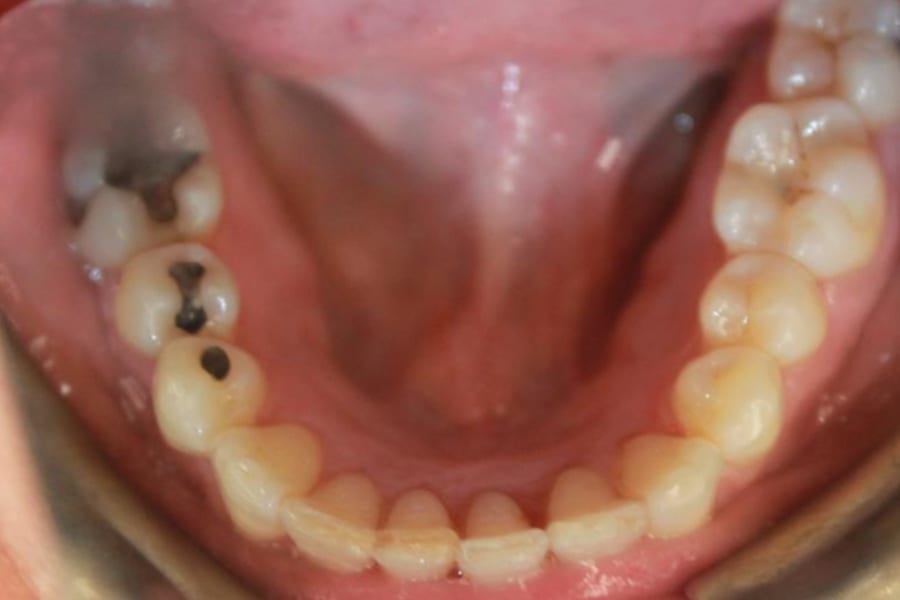

A 54-year-old woman presented with a chief complaint of teeth crowding. After comprehensive digital records were obtained, ClearCorrect® aligner therapy (Straumann, clearcorrect.com) was chosen with an anticipated 12-month treatment duration. The patient exhibited moderate anterior crowding, a class II molar relationship, and narrow arches. The treatment plan aimed to resolve the class II discrepancy, expand the arches, and establish proper anterior alignment. A total of 25 active aligners plus two retention aligners were prescribed. Attachments were selectively placed on the maxillary and mandibular canines to premolars, minimizing bulk while maintaining control over torque and posterior alignment. The patient was instructed to wear class II elastics full-time, which was crucial to achieving molar correction and arch expansion. Her outstanding compliance with class II elastics contributed to a significant improvement in molar position and transverse arch development. After completing the active phase, the patient transitioned to retainers to ensure long-term stability of the results. Given the patient’s initial class II occlusion, monitoring retention was emphasized to prevent relapse. The patient was extremely pleased with the outcome, demonstrating a broadened smile and improved occlusal function. This case underscores the effectiveness of ClearCorrect’s aligners in adult patients, particularly when combined with compliant elastic wear and targeted expansion strategies.